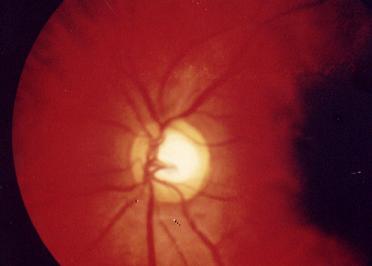

视神经乳头杯状凹陷

眼睛,眼科,眼科图谱,视神经乳头杯状凹陷